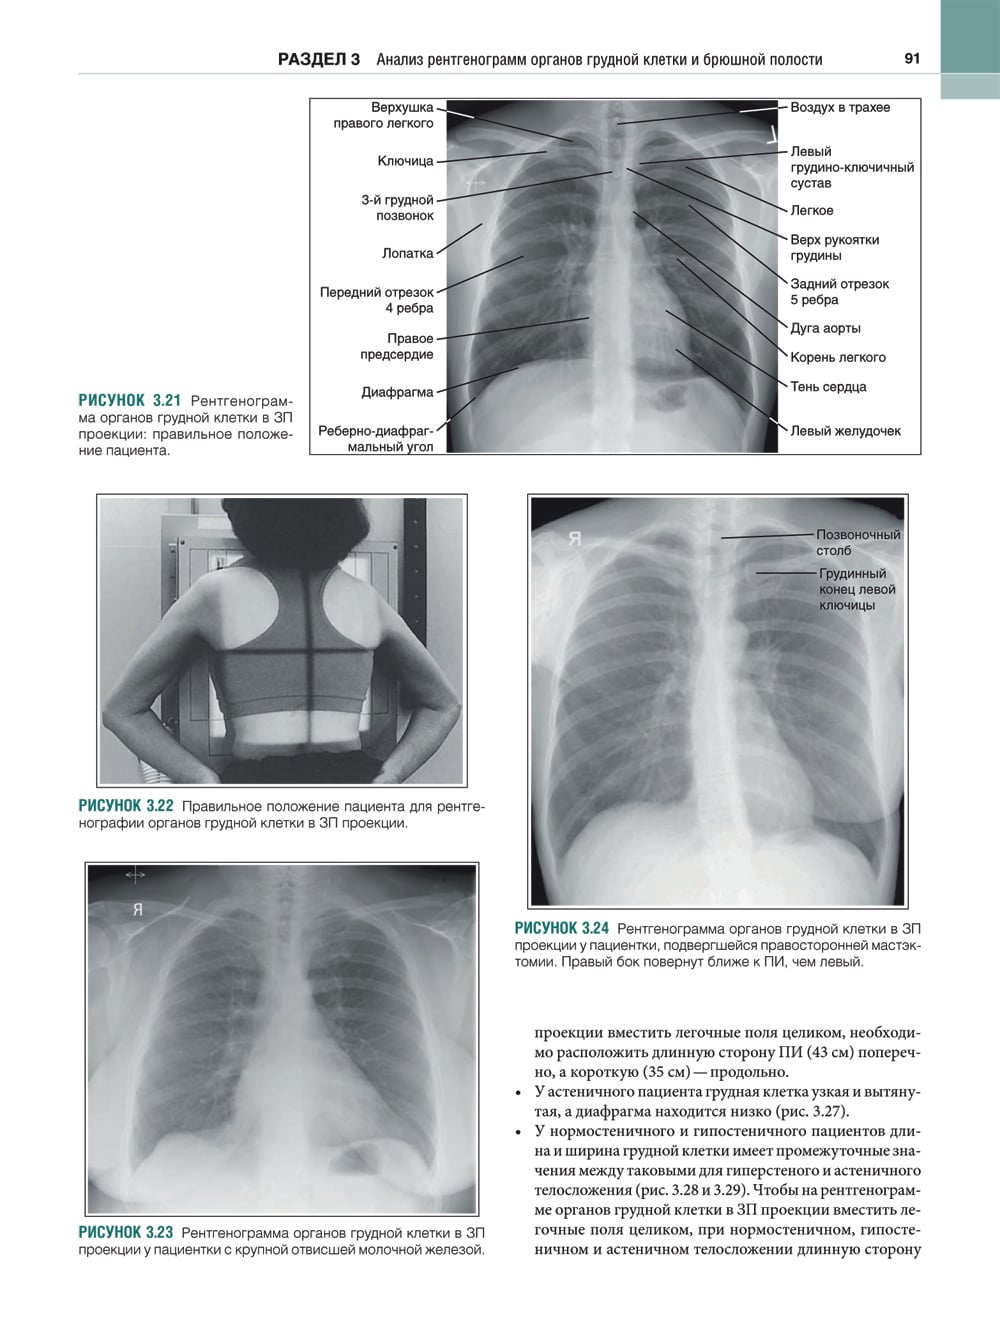

В этом практическом руководстве описаны основные методики выполнения рентгенографии и принципы анализа качества рентгенограмм, стандартные технические параметры исследования, а также варианты укладки и способы их коррекции. Особое внимание уделено базовым принципам получения и цифровой обработки изображений. Для каждой рентгенологической методики приведены фотографии правильной укладки пациента, варианты укладки в нестандартных ситуациях и при определенных патологических состояниях, а также таблицы с сопоставлением вариантов укладки, примеры определения центрального луча или приемника изображения, рисунки и фотографии костных препаратов и условного пациента, позволяющие точнее отобразить взаимное расположение анатомических структур, если проекционное искажение затрудняет интерпретацию рентгенограмм. Издание содержит более 1500 иллюстраций. Книга предназначена для рентгенологов.| Издательство | ИЗД.ПАНФИЛОВА |